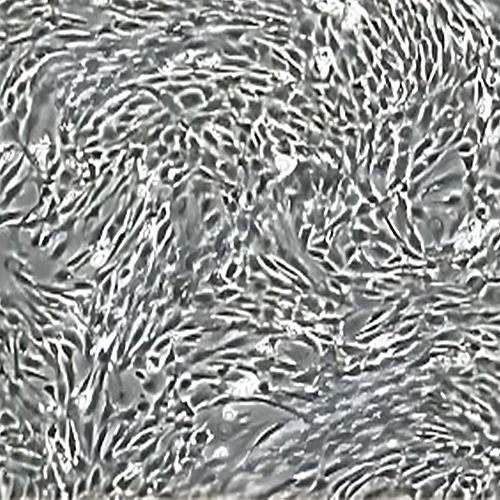

SD-大鼠骨髓間充質(zhì)干細(xì)胞